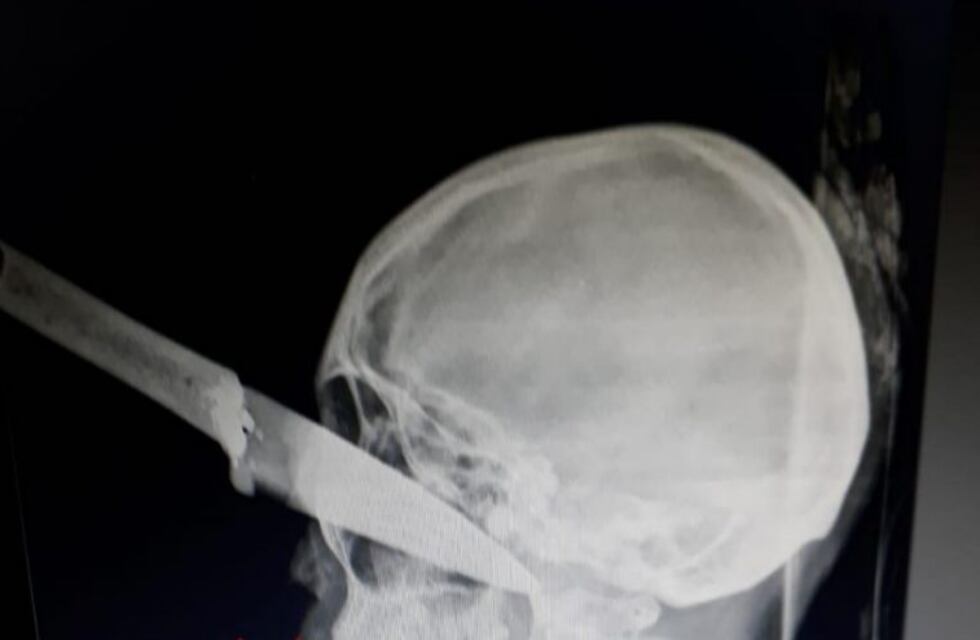

El arma atravesó el ojo de la víctima, recibió primeros auxilios y fue trasladada al hospital San Bernardo, donde tras una cirugía con dos equipos médicos está con pronóstico reservado.